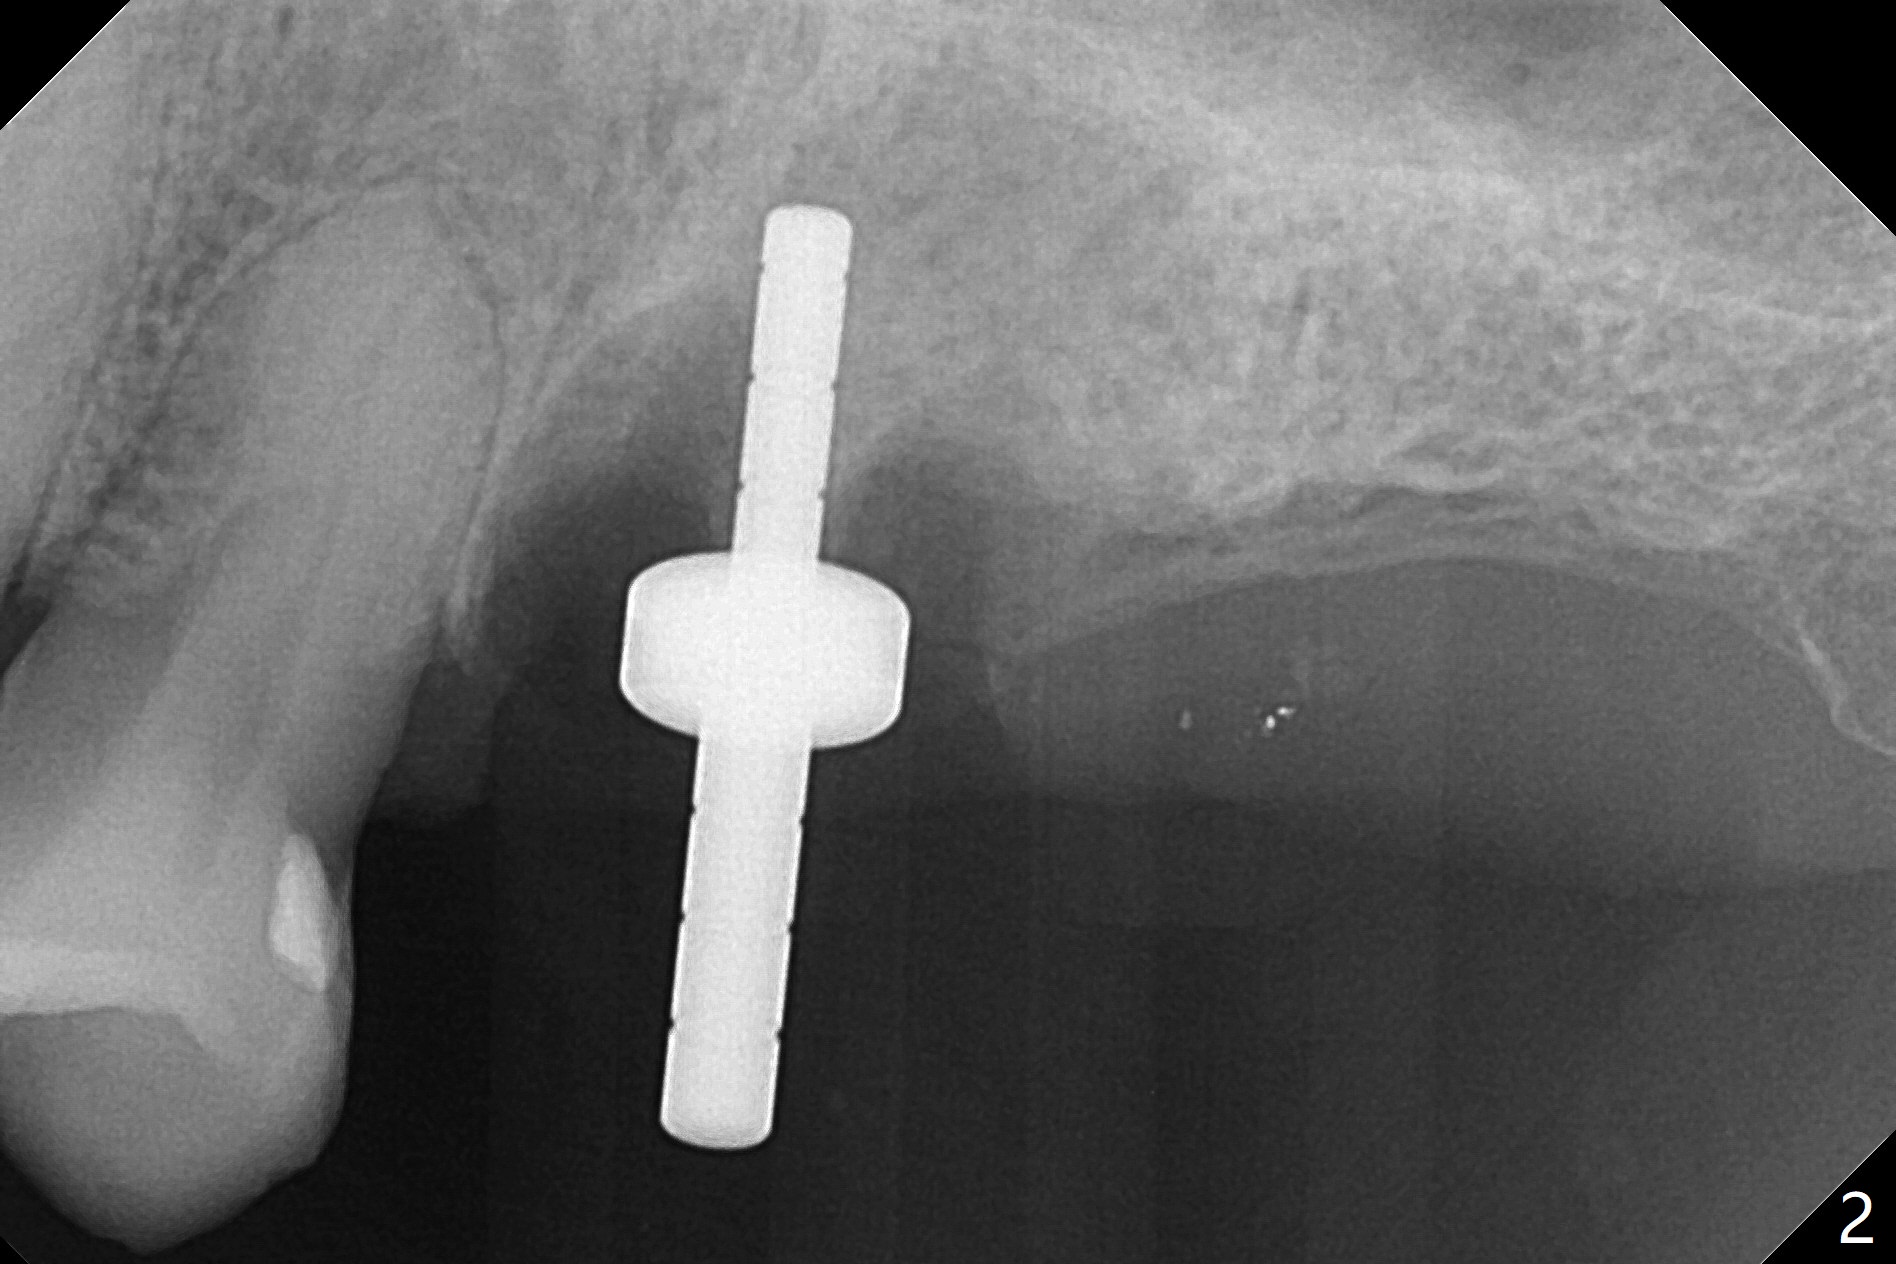

After extraction of the tooth #14 (Fig.1) and removal of granulation tissue associated with a distal fistula, a 1.6 mm drill is used to initiate osteotomy in the septum for 9 mm, followed by insertion of a 7 mm long parallel pin (Fig.2).  The length of the subsequential osteotomy is 11 mm until 4.8 mm in diameter (overprep as will be shown below).  The bone is hard so that sinus lift fails with 4.8 mm Magic Expander.  Since a 5x9 mm dummy implant is placed with stability, a definitive implant with the same dimension is chosen with >50 Ncm (Fig.3,4).  Prior to and after abutment placement, Vera graft is placed (*).  The provisional perforates with loose abutment 3.5 months postop.  A 6x4 mm healing abutment is placed.  Osteointegration occurs 4 months postop (Fig.5,6).